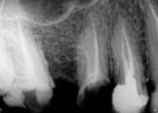

antes depois